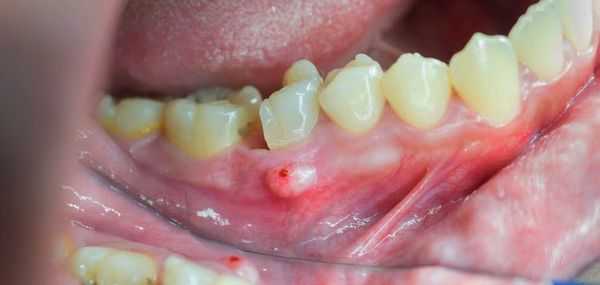

После острой стадии наступает подострая. На десне образуется гнойничок или свищ, через который гнойные выделения и воспалительная жидкость выходят наружу.

Наконец, как внутриротовые, так и внеротовые свищи обычно присутствуют при хронической фазе остеомиелита челюстно-лицевой области.